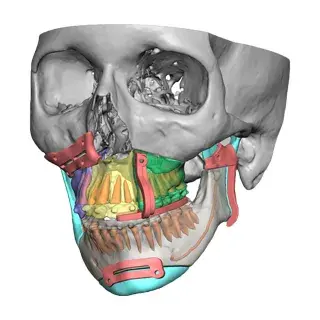

3D Systems' VSP® surgical planning solutions for craniomaxillofacial (CMF) applications received FDA clearance as a service-based approach to personalized surgery over 10 years ago.

3D Systems and Stryker Corporation have partnered to provide surgeons with best-in-class products and services for craniomaxillofacial surgeries. As a leader in personalized healthcare solutions, 3D Systems has planned and delivered devices for more than 140,000 patient-specific cases. The Stryker Craniomaxillofacial business specializes in providing patient-specific options and innovative solutions that help drive efficiencies in surgical suites. The combination of Stryker’s specialized team and advanced implants with 3D Systems' cutting-edge 3D printing technologies and expert consulting services positions both companies to provide a superior level of service to healthcare professionals who use these revolutionary solutions.